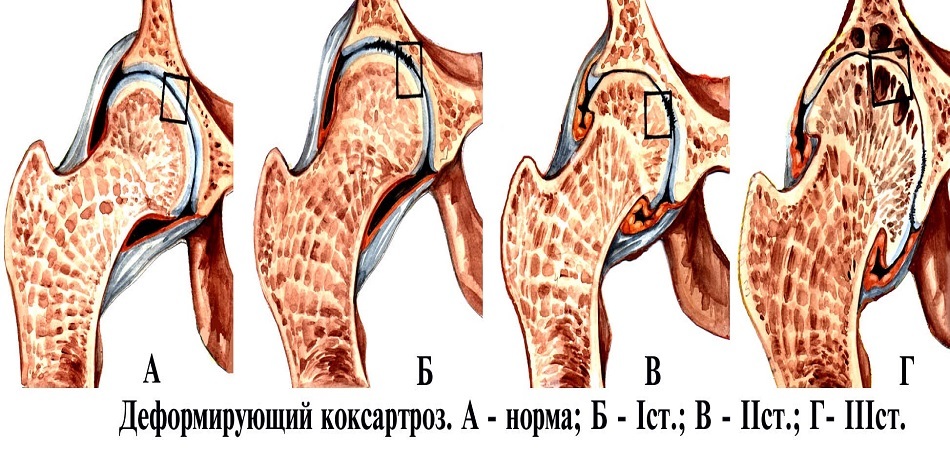

Ранние проявления коксартроза у взрослых

Современная статистика свидетельствует о неуклонном росте заболеваемости опорно-двигательного аппарата. Коксартроз занимает одно из первых мест среди дегенеративно-дистрофических заболеваний опорно-двигательного аппарата. Свидетельством актуальности данной проблемы служит посвящение большого числа различных конференций и симпозиумов, появление значительного количества публикаций по диагностике и лечению артрозов.

На рентгенограммах тазобедренный сустав сохраняет нормальную форму, суставная щель умеренно или неравномерно сужена с субхондральным склерозированием костных суставных поверхностей, непостоянными краевыми костными разрастаниями (I стадия).

Рентгенологически суставная щель может быть равномерно или неравномерно сужена, ацетабулярная суставная впадина уплощена, присутствуют явления субхондрального склероза, краевые костные разрастания. Конфигурация головки бедренной кости, как правило, не нарушена (II стадия).